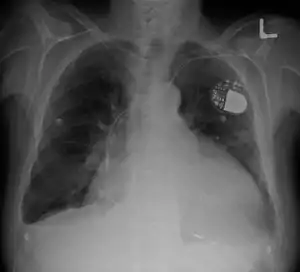

| Cardiomegaly on chest X-ray with a pacemaker | |

- Chest X-Ray: X-ray images help to visualize the condition of the lungs and heart. If the heart is enlarged on an X-ray, other tests will usually be needed to find the cause. A useful measurement on X-ray is the cardio-thoracic ratio, which is the transverse diameter of the heart, compared with that of the thoracic cage.[24] These diameters are taken from PA chest x-rays using the widest point of the chest and measuring as far as the lung pleura, rather than lateral skin margins. If the ratio is greater than 50%, pathology is suspected.[25] The measurement was first proposed in 1919 to screen military recruits. A newer approach to using these x-rays for evaluating heart health takes the ratio of heart area to chest area and has been called the two-dimensional cardiothoracic ratio.[26]

- Pacemaker: Coordinates contractions between ventricles. In people at risk of arrhythmias, drug therapy or an implantable cardioverter-defibrillator (ICD).